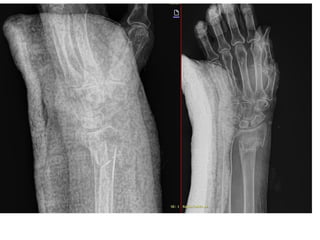

NOMBRE: BALTAZAR JUAREZ OFELIA

NSS: 01794924611 5F1949PE

URG A

Edad: 76 AÑOS

Comorbilidades: NA

Fecha de la lesión: 19/09/2025

Mecanismo de lesión: CAIDA DE SU PLANO DE SUSTENTACION CON CARGA AXIAL

Laboratorios: EN ORDEN

Valoraciones: NA

Diagnósticos: FRACTURA RADIOCUBITAL DISTAL IZQUIERDA FRYKMAN VIII

Cirugía Proyectada: REDUCCION ABIERTA CON FIJACION EXTERNA CON COLOCACION DE PEQUEÑOS FIJADORES EXTERNOS

Material OSS Solicitado: FIJADORES EXTERNOS

NOMBRE: BALTAZAR JUAREZOFELIA NSS: 01794924611 5F1949PE URG A Edad: 76 AÑOS Comorbilidades: NA Fecha de la lesión: 19/09/2025 Mecanismo de lesión: CAIDA DE SU PLANO DE SUSTENTACION CON CARGA AXIAL Laboratorios: EN ORDEN Valoraciones: NA Diagnósticos: FRACTURA RADIOCUBITAL DISTAL IZQUIERDA FRYKMAN VIII Cirugía Proyectada: REDUCCION ABIERTA CON FIJACION EXTERNA CON COLOCACION DE PEQUEÑOS FIJADORES EXTERNOS Material OSS Solicitado: FIJADORES EXTERNOS